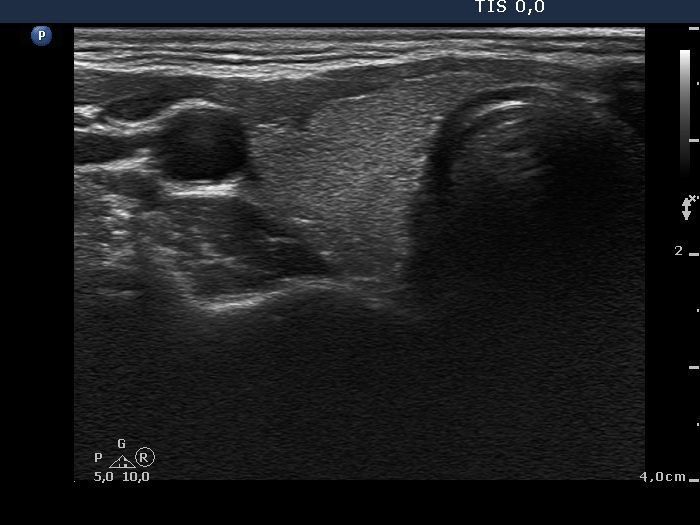

Right lobe, transverse scan

This is the usual course of Graves' disease regarding the change in echo pattern - before, during and after the activity of the autoimmune process. The only exception is the change in the size of the thyroid. In most cases, the thyroid increases during the activity of the disease, then returns to normal. However, in this patient the age counts: at the first examination, the patient was only 15-year-old.